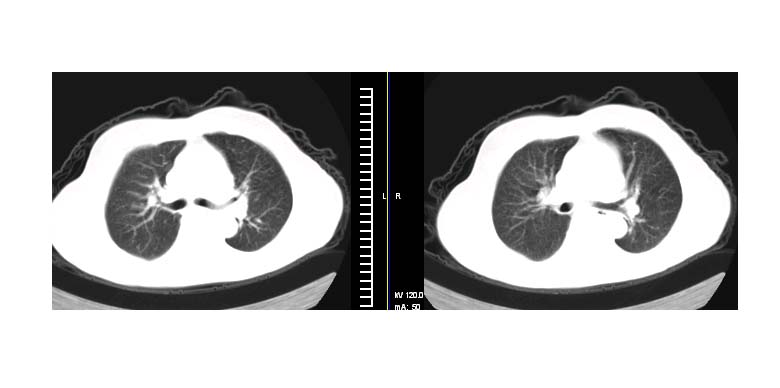

标题: CT11087:男性,82.咳嗽一周.抗炎治疗4-5天效果不明 [打印本页]

标题: CT11087:男性,82.咳嗽一周.抗炎治疗4-5天效果不明

考虑左上肺癌,似与左侧肋骨关系密切?

左上肺实质性肿块,浅分叶 毛糙 胸膜凹陷征 纵隔淋巴结肿大——支持:左肺上叶周围型肺癌!

左上肺软组织肿块,有分叶,短毛刺,气管旁间隙见有肿大淋巴结,考虑左上周围型肺癌伴纵隔淋巴结转移。